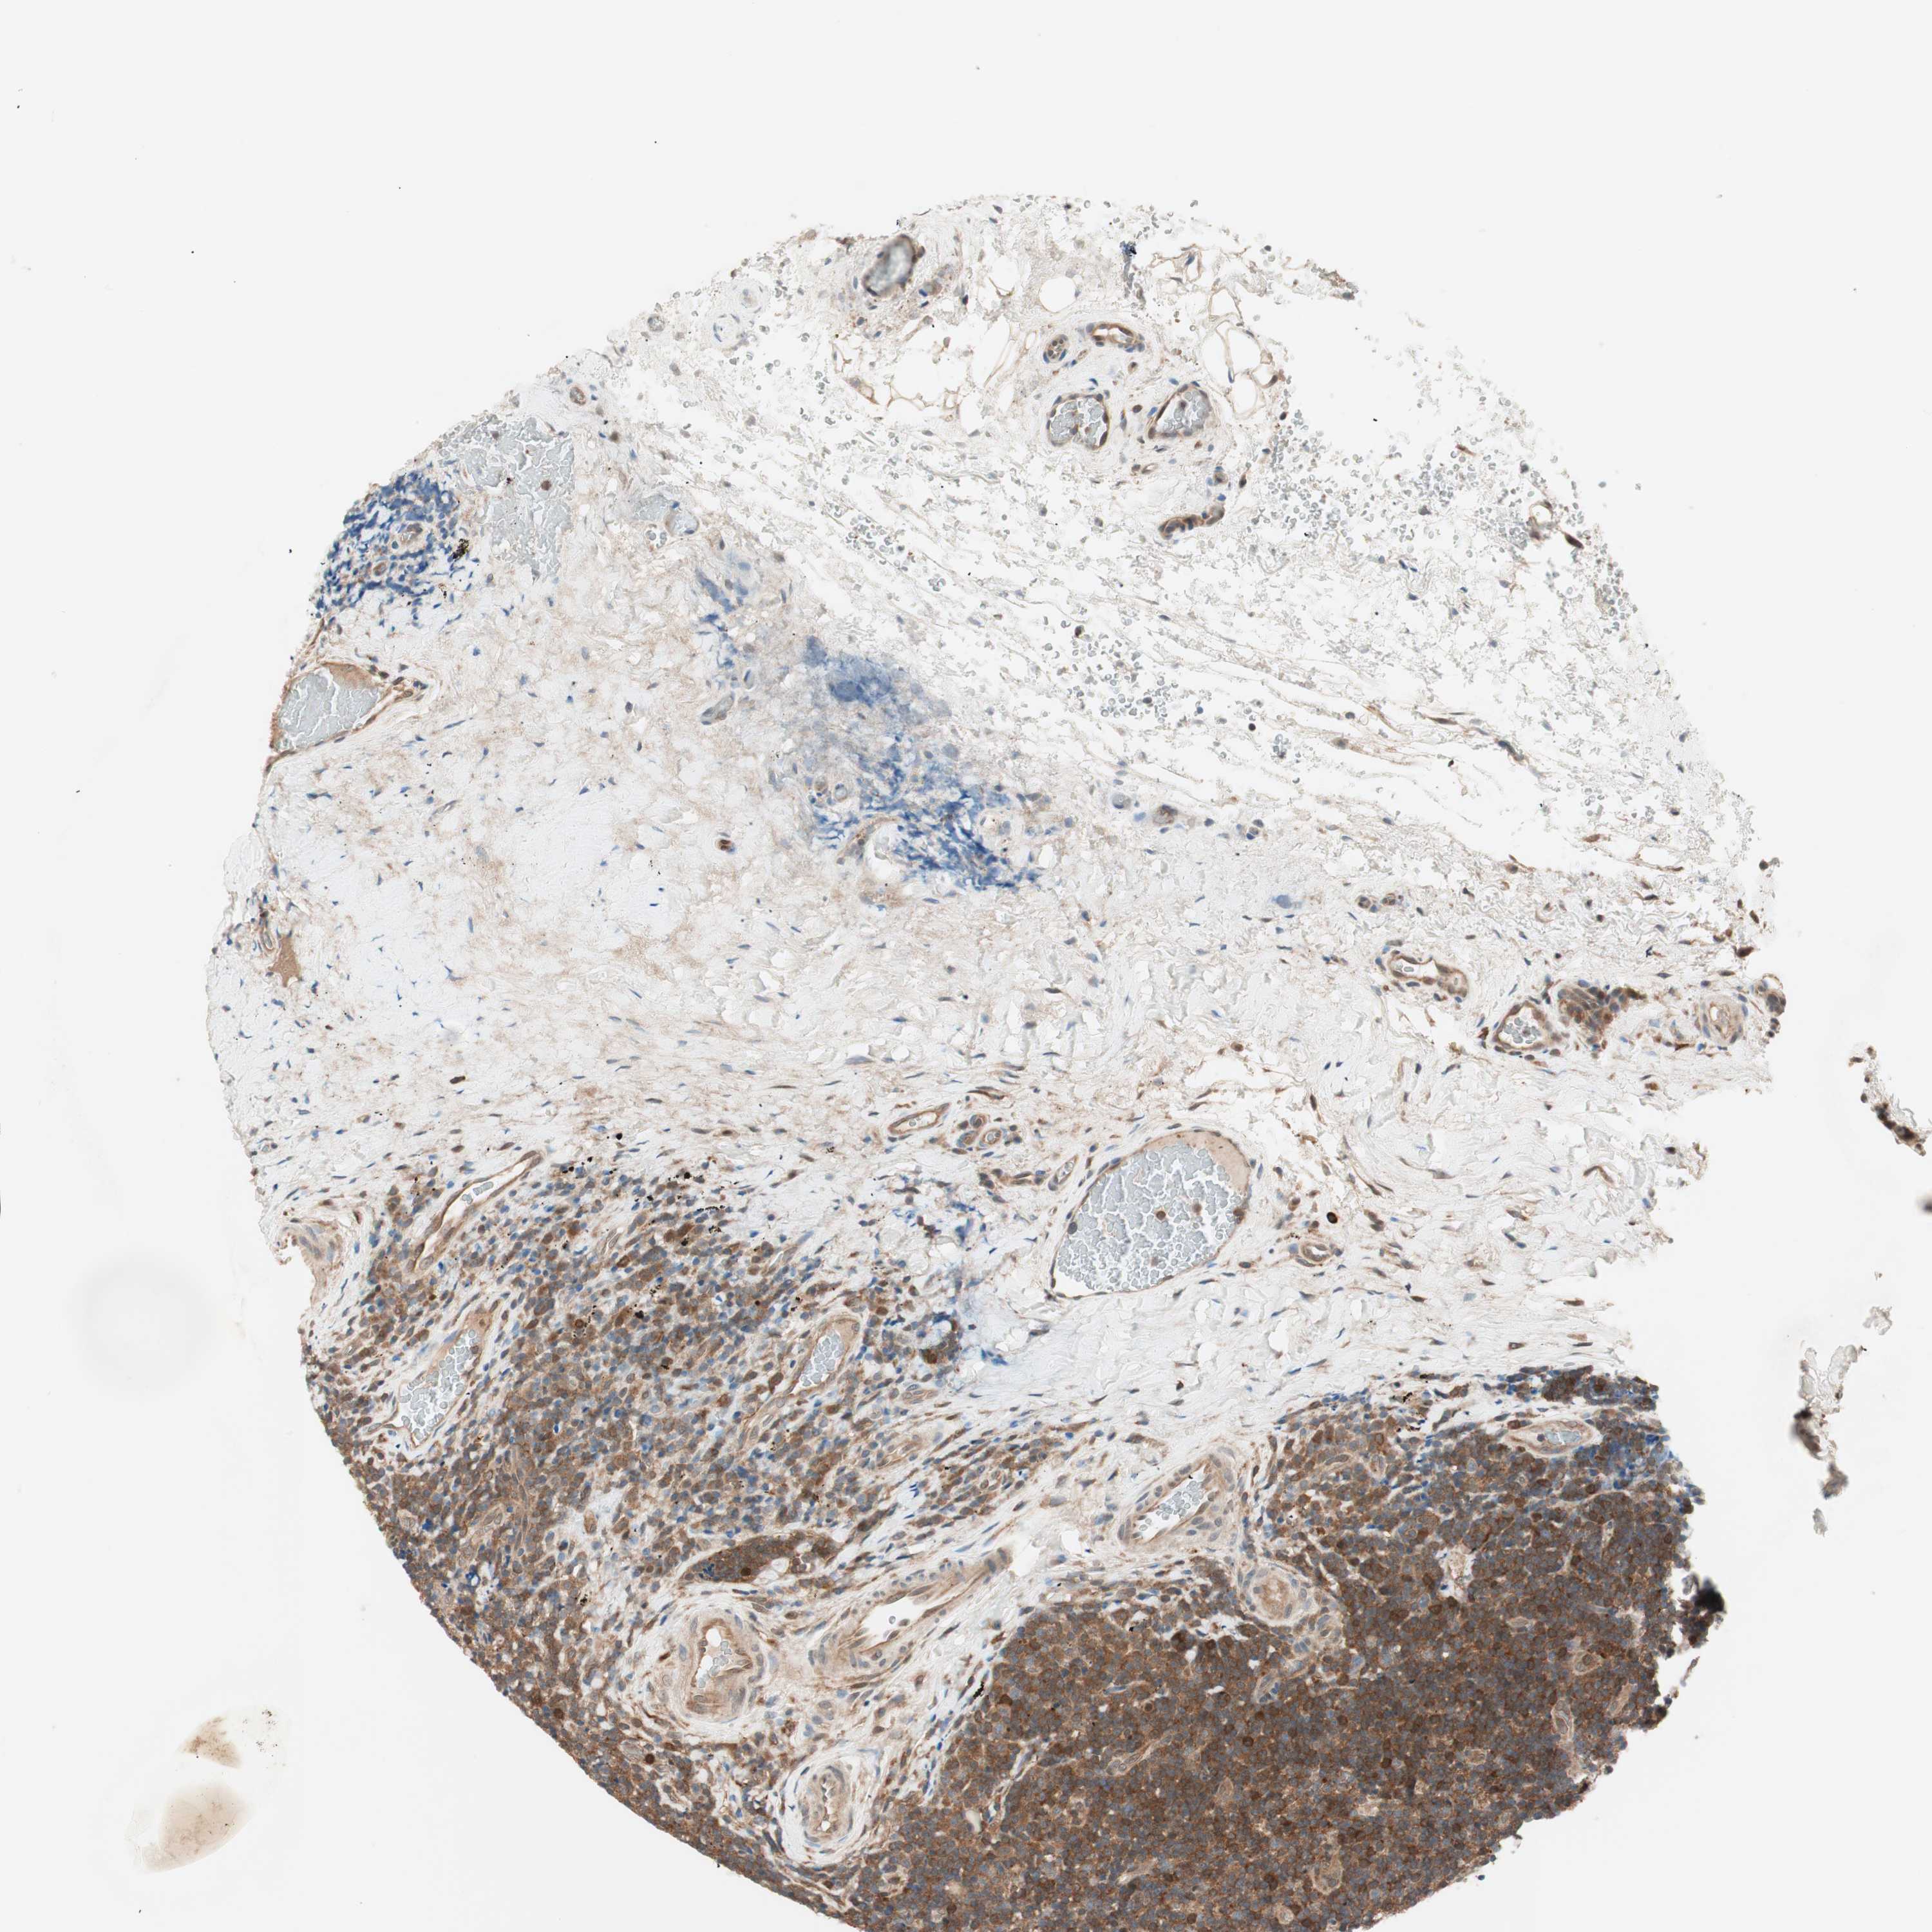

LYMPHOMA - Protein expressioni

A mouse-over function shows sample information and annotation data. Click on an image to view it in a full screen mode. Samples can be filtered based on level of antibody staining by selecting one or several of the following categories: high, medium, low and not detected. The assay and annotation is described here.

Antibody stainingi

Antibody staining in the annotated cell types in the current human tissue is reported as not detected, low, medium, or high, based on conventional immunohistochemistry profiling in selected tissues. This score is based on the combination of the staining intensity and fraction of stained cells.

Each image is clickable and will lead to virtual microscopy that enables deeper exploration of all samples and also displays staining intensity scores, fraction scores and subcellular localization as well as patient and tissue information for each sample.

Antibody HPA004868

Antibody HPA005729

Staining

High

Medium

Low

Not detected

Intensity

Strong

Moderate

Weak

Negative

Quantity

>75%

75%-25%

<25%

None

Location

Nuclear

Cytoplasmic/membranous

Cytoplasmic/membranous,nuclear

Hodgkin's disease, NOS

Malignant lymphoma, non-Hodgkin's type, Low grade

Malignant lymphoma, non-Hodgkin's type, High grade